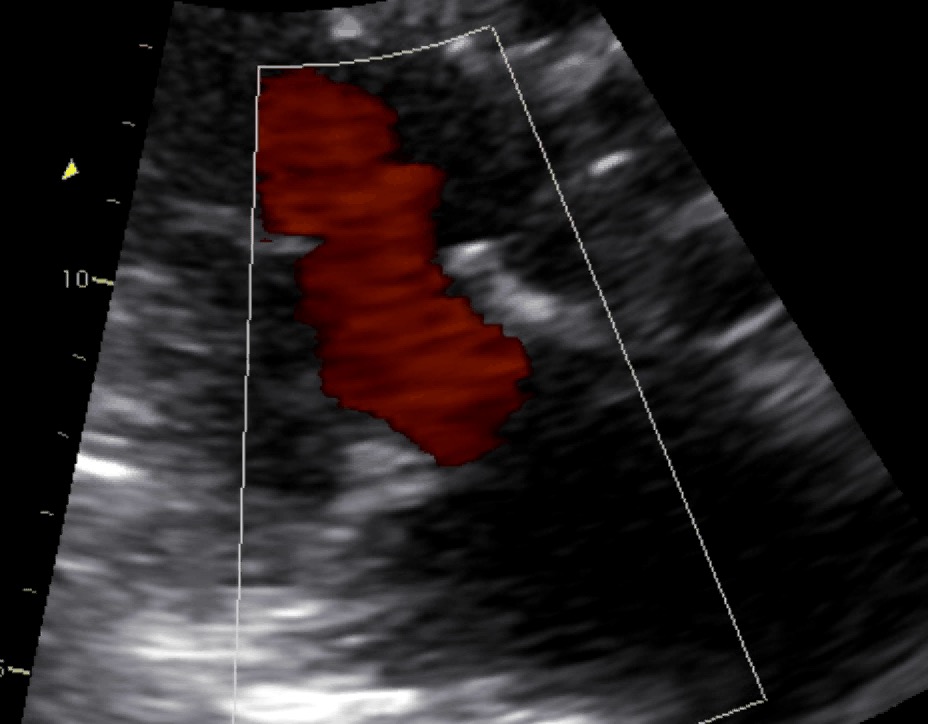

Protesi biologica mitralica Carpentier 25Autore: Daniela Torta

Categoria: Videoalbum

Parole chiave: biologica diagnosi ecotee3d protesi -